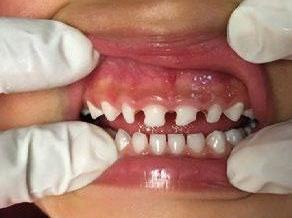

Figura 1. Foto inicial de la paciente.

Paciente femenina de 3 años de edad que requiere rehabilitación de los incisivos superiores, la madre de la paciente solicita que el tratamiento sea lo más conservador y estético posible.

El requerimiento estético por parte de la madre de la paciente es fundamental para la decisión de la confección del plan de tratamiento, selección del material y preparación de la restauración (Figura 1).